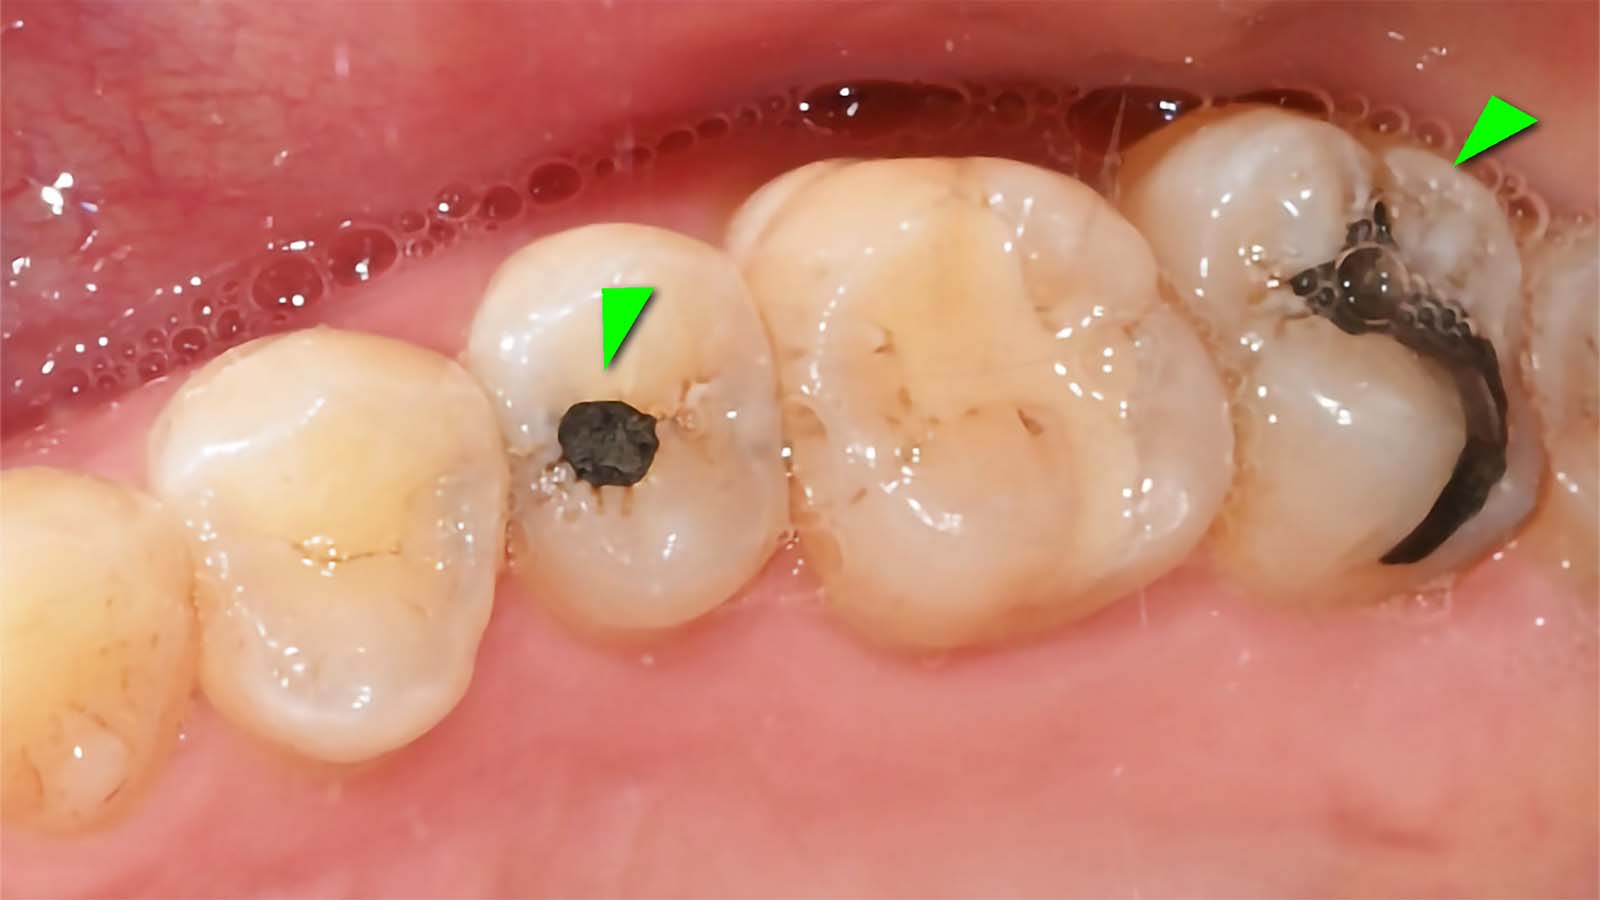

아말감 치료

아말감 사이 치아는 GI로 치료한 결과

오른쪽 아말감 부분에 충치가 생겨서 레진빌드업으로 치료한 결과입니다. 왼쪽부터 아말감, GI, 레진 순서입니다. 아말감은 검고, GI는 치아와 비슷하지만 다르고, 레진은 자연 치아와 구분이 안됩니다.